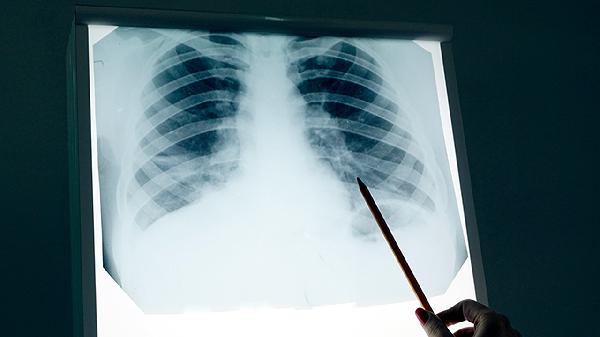

肺癌患者可通过手术治疗、放射治疗、化学治疗、靶向治疗、免疫治疗等方式治疗。肺癌通常与吸烟、职业暴露、空气污染、遗传因素、慢性肺部疾病等原因有关,表现为咳嗽、咯血、胸痛、呼吸困难、体重下降等症状。